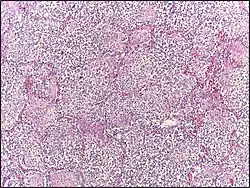

Reactive hyperplasia of lymph node | Histopathology of a reactive lymph node by the cystic duct in a case of cholecystitis. | Category: Reactive hyperplasia of lymph node | Reactive hyperplasia |

![]() |